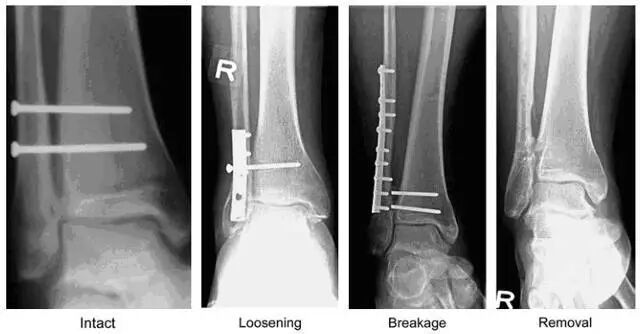

图 1  下胫腓联合螺钉示意图。由左向右分别为完整、松动、断裂、取除后的下胫腓联合螺钉(图片来自文献 [1])

最传统、最常用的固定方式为用 1 枚或多枚螺钉对下胫腓联合进行固定。关于下胫腓联合螺钉的数量、直径、位置、固定三或四层皮质、是否取出等有很多文献,但是结果均不确定,无法判断哪种选择更好。

但是,无论哪种选择,都可以使下胫腓联合得到有效固定。一般在 8~12 周后下胫腓联合韧带即可愈合,此时螺钉的存在已无必要。但学界对于是否需要取除这些已无存在必要的螺钉一直存在争议。

支持取除的学者认为,下胫腓联合是微动关节,在行走过程中关节间隙将会变宽,下胫腓联合螺钉的存在会限制这种变化,从而影响踝关节的活动。这些学者主张应在术后 10~12 周时将螺钉取除,从而使踝关节可以自由活动并避免螺钉断裂。

然而,有研究表明即使保留下胫腓联合螺钉对患者的功能预后也无明显影响,取除螺钉还会增加并发症的风险和患者的经济负担。因此,也有学者认为无需常规取除该螺钉。